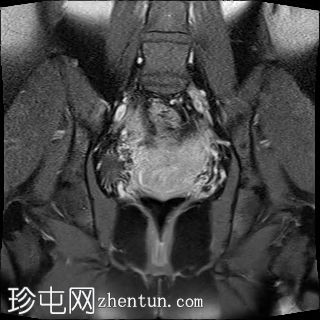

冠状位

T2加权像

双侧卵巢位置接近(卵巢相吻),左侧卵巢内可见一边界清晰的囊性病变,大小约3.1 × 2.7 × 2.9 cm,T1加权像呈高信号,T2加权像可见暗点征及内部暗点征。以上MRI特征符合卵巢子宫内膜异位囊肿的诊断。

右侧卵巢可见一囊肿,大小约为 2.8 × 2.0 × 2.2 cm,T1 加权像呈高信号,囊内可见液-液平面,提示囊内含有不同时期的出血性物质。由于对侧卵巢存在典型的子宫内膜异位囊肿,且该囊肿无强化,影像学表现强烈提示为另一子宫内膜异位囊肿。

双侧卵巢囊性病变,MRI 表现符合子宫内膜异位囊肿的特征,左侧较大。未见强化壁结节或实性成分,提示无恶性转化。